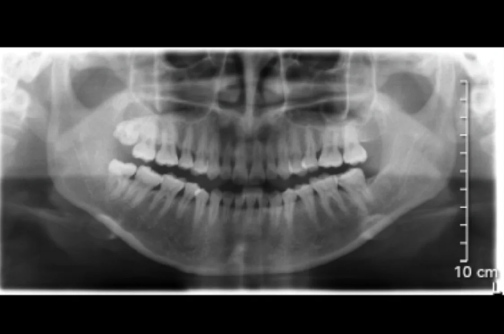

对于一些牙周炎比较严重的患者,龈下刮治可能是必要的治疗措施之一。牙周炎是一种常见的口腔疾病,它是由牙齿周围的牙龈组织受到炎症损害引起的。如果不及时治疗,牙周炎可能会导致牙齿松动、牙齿脱落等问题。

龈下刮治是通过专业的器械对于龈下的牙周组织进行深度清洁,包括根面清洗和病理性软组织的处理。这可以去除龈下的菌斑和牙石,减少牙齿周围的炎症,促进口腔组织愈合,从而达到预防和治疗牙周炎的目的。